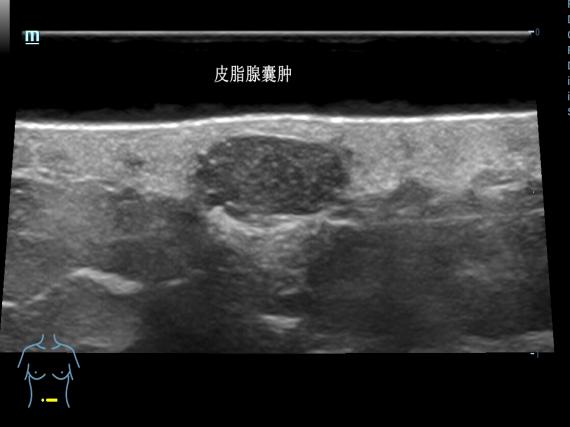

传统皮肤科诊断主要靠眼睛观察、手触摸,或取一点皮肤组织做病理检查,很难直接看到深层的情况。超高频超声(通常指频率在20MHz以上的超声),提供了新的观察维度——20MHz超高频超声可分辨0.1mm的病灶,70MHz超声高频超声可以分辨0.03mm病灶。

通过分析病灶的形态、边界特征和内部血供情况,医生能够更准确地区分炎症性病变、良性增生性病变与恶性肿瘤。